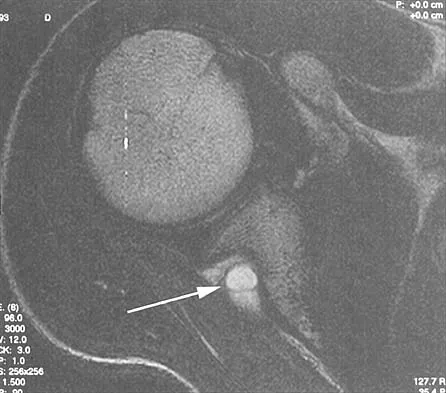

Question 23

A coronal MRI scan through the shoulder joint is shown in Figure 26. The cyst indicated by the arrow will most likely cause compression of what nerve?

Explanation